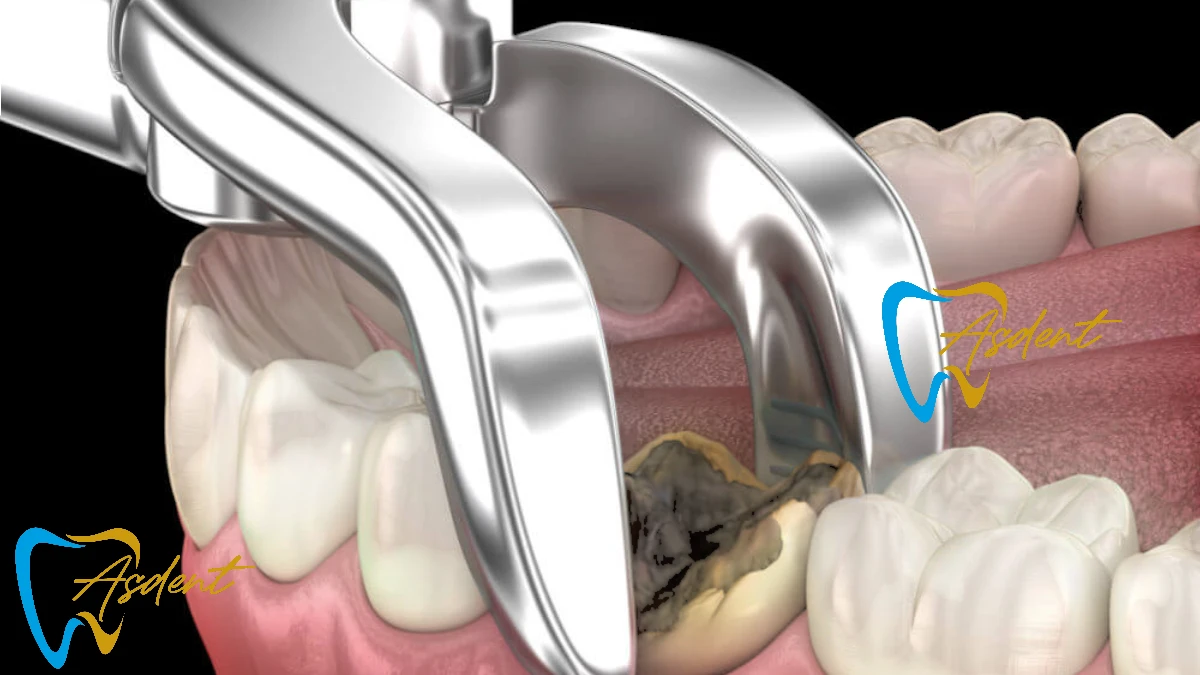

Удаление зуба — это процедура удаления зуба из его лунки в кости. Эта процедура часто необходима, если зуб серьёзно повреждён, разрушен или вызывает другие стоматологические проблемы. В стоматологической поликлинике АСДЕНТ мы выполняем как простые удаления (для видимых зубов), так и хирургические удаления (для ретинированных или разрушенных зубов).

При простом удалении зуб аккуратно расшатывается и извлекается. При хирургическом — делается разрез для доступа к зубу или области. - Шаг 4: Рекомендации по уходу